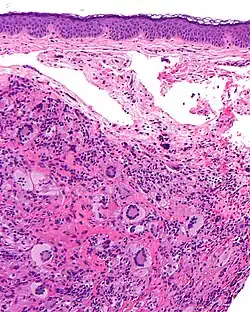

Mikrofoto von Langerhans-Zell-Histiozytose, eine Histiozytose. HE-Färbung.